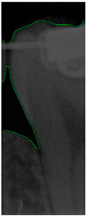

Image-enhancement results: (a) binarization; (b) mathematical morphology; (c) added green line represents canny; (d) overlap onto the original image.

2.3.4. Mathematical Morphology

This study utilized morphological operations to improve the success rate of edge detection. Morphological operations are fundamental operations in mathematical morphology, which are primarily used to enhance specific features of images such as edges, shapes, and structures that are widely applied in image processing. Opening and closing are the two main operations, and their formulas are as shown in (2) and (3). These operations are based on combinations of dilation and erosion. The opening operation removes small objects or spots from an image, while the closing operation fills in small holes or gaps in an image. The results of morphological operations are shown in Figure 8b.

2.3.5. Canny Edge Detection

Since filtered and binarized images alone cannot enhance the features of dental calculus, this approach does not effectively improve the accuracy of machine learning. Therefore, this study employed edge detection to identify the contours of tooth edges, enhancing the regions of interest and thereby improving the accuracy of machine learning. The canny edge-detection algorithm applies non-maximum suppression to each pixel, retaining pixels with local maximum gradient values, which can produce continuous and accurate edges while demonstrating good resistance to noise. The edge-detection results are represented in green, as shown in Figure 8c. Finally, these results are overlaid back onto the original image, as illustrated in Figure 8d.